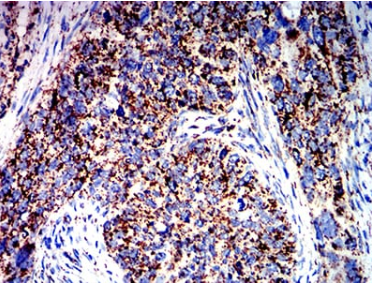

Species Reactivity    Human

Immunogen    Purified recombinant fragment of human ATPIF1 (AA: 1-106) expressed in E. Coli.

IHC    1/200 - 1/1000